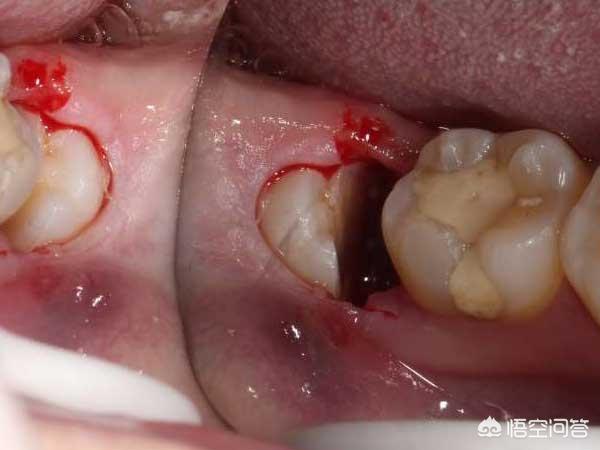

干槽症要怎么处理?

1、局部麻醉下彻底清创,去除牙槽窝内的感染物,最后放入碘仿纱条,创口较大的缝合两针,一周后再取掉,创口小的2~3天更换一次碘仿纱条,直到覆盖住的肉芽组织长出为止,剩下的交给时间慢慢愈合,差不多三个月左右牙槽窝就能长平。

2、如果是干槽症早期还能搔刮干净,等血凝块充盈后,再咬住纱布止血就可以了。